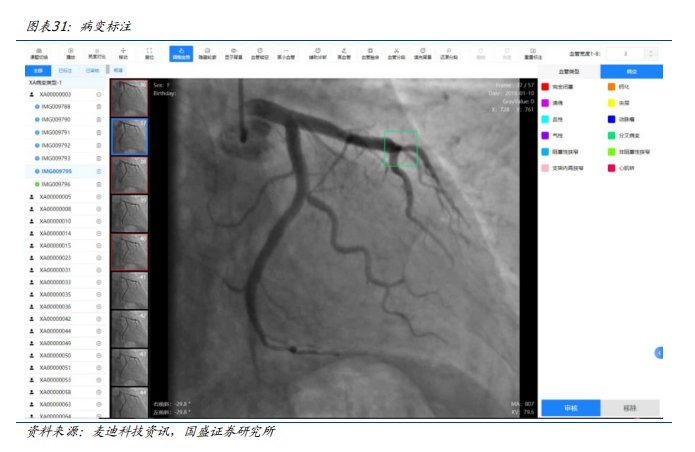

早在2023年,由麦迪科技研发的心血管医学影像人工智能科研平台在复旦大学附属中山医院落地。该项目是基于复旦大学附属中山医院在心血管疾病方向的学科集群优势,研发的一款与影像大数据库连接的“一站式”心血管医学影像人工智能科研平台,实现科研影像数据的快速收集,以及人工智能科研所需的标注、清洗、存储、训练和验证等功能。

心血管医学影像人工智能科研平台是基于计算机视觉网络模型的人工智能技术框架作为AI基础服务层,打造心血管人工智能影像分析平台为临床提供辅助诊疗服务。包含冠脉造影、血管内超声及CT血管造影等心血管疾病影像检测智能分析功能。通过对冠脉造影血管轮廓智能提取可以快速定位血管狭窄,完成血管狭窄分析,实现狭窄血管重建与定量测算,分析计算狭窄的功能学指标参数;同时还提供手术支架建议,便于快速制定介入手术方案。通过血管内超声影像分析可以快速完成血管内超声图像分析,实现斑块定位与测算,便于快速制定后续的治疗方案。